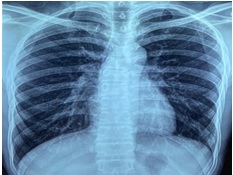

A 38-year-old man presented to the respiratory OPD with complaints of fever, chest pain, and cough. He had these symptoms for 4 months. The patient didn’t suffer from any chronic disease or co-morbidities. He didn’t undergo any clinical procedures. Complete blood count and biochemical investigations were normal. A Chest X-ray demonstrated left lower zone opacity ([Figure 1]). It was confirmed to be an alveolar opacity (without air bronchogram) in the posterior and lateral basal segment of the left lower lobe on computerized tomography of the thorax ([Figure 2]). The sputum cartridge-based nuclei amplification test for negative for tuberculosis. A bronchoscopy was done to collect bronchial wash for culture. Mycobacterium abscessus was isolated via matrix-assisted desorption isonization- time of flight mass spectrometry. The drug sensitivity testing was also performed and the sensitivity pattern is given in [Table 1]. A drug regime consisting of intravenous amikacin, oral linezolid, clarithromycin, and moxifloxacin was started. This regime was designed to follow the drug sensitivity pattern and patient preferences.The patient was reassessed after 1 month of treatment. The symptoms had resolved, and the X-ray opacity had cleared ([Figure 3]).

The symptoms of the M. abscessus infection depend upon the involved system. Respiratory system involvement presents with symptoms of chronic cough, fever, and chest pain. Often the chronicity of the symptoms is due to the delay in the diagnosis. In our case, the patient had symptoms of cough and chest pain for 4 months. In a TB-endemic country like India, the diagnosis is often delayed due to considerable overlap between the symptomatology of the mycobacterium tuberculosis and abscessus. Chest radiography showed left lower zone opacity in our patient. It was confirmed to be an alveolar mass without an air bronchogram in the left lower lobe on computerized tomography of the thorax. M. Abscessus presents with tree-in-bud appearance (nodules), bronchiectasis, and cavitation. [4], [5] There is no zonal or lobar preponderance. Mediastinal lymphadenopathy is less common. NTM are known to present as lung masses. This type of presentation is commonly seen with mycobacterium avium complex. [6] Due to the non-specificity of the clinical features, microbiological confirmation remains the only method of diagnosis. Sputum, protected bronchoscopic brush sample, or bronchial wash are used to culture the organism in the lab. In accordance with the national tuberculosis elimination programme guidelines, the patient was offered a sputum cartridge-based nucleic acid amplification test. The result was negative for tuberculosis. To confirm the diagnosis, the patient underwent a bronchoscopy. M. Abscessus was isolated by Matrix-assisted desorption isonization- time of flight mass spectrometry from the bronchial wash.